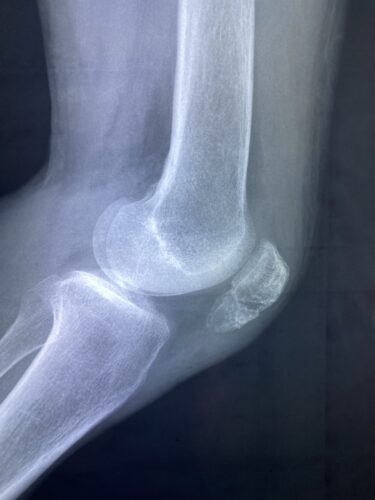

第28回整骨研究会「賜恩」研究会を開催し、上腕骨顆上骨折伸展型の研修をし…

第28回整骨研究会「賜恩」研修会開催

春日部市市民活動センター(上腕骨顆上骨折)

小児上腕骨外顆回転骨折の1症例について

肘関節前方脱臼の1症例について